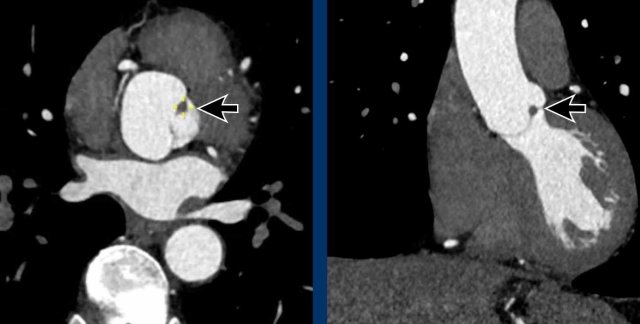

Papillary fibroelastoma of the Aortic valve

A rare finding is a papillary fibroelastoma (arrow), which is the commonest primary tumor in relation to the cardiac valves, mainly in relation to the aortic or mitral valve.

The typical CT finding of a PFE is a small irregular pedunculated mass in relation to the heart valve.

Most often it is an asymptomatic incidental finding, although a papillary fibroelastoma can be complicated by systemic embolic events.